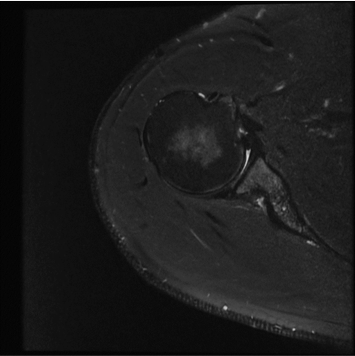

standard

384 x 256 (4 NEX)

3:02 minIAI (Innovative AI)

384 x 256 (2 NEX)

1:30 minReduced Scan Time

384 x 256 (2 NEX)

1:30 minstandard